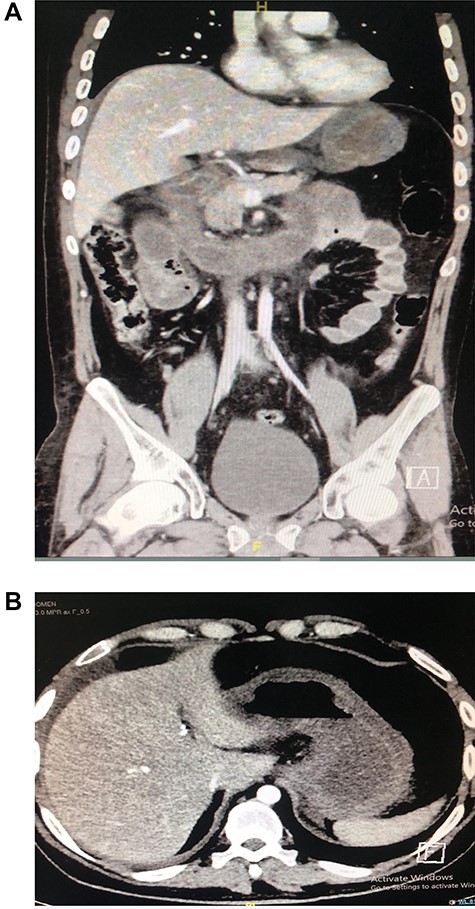

A 30-year-old male patient presented to emergency department with epigastric abdominal pain for 30 minutes after flash material ingestion. He was conscious, oriented, with vital signs remarkable for tachycardia; abdominal examination was soft with epigastric tenderness. Lab investigations were haemoglobin: 17, white blood cell: 19, normal renal profile and amylase. Computed tomography (CT) abdomen was done and showed signs of small bowel obstruction associated with segmental small bowel ischaemic changes (Fig. 1a and b).

(A and B). CT showing segmental dilatation of the small bowel with diffuse circumferential wall thickening and suspected tow areas of transnational zones.